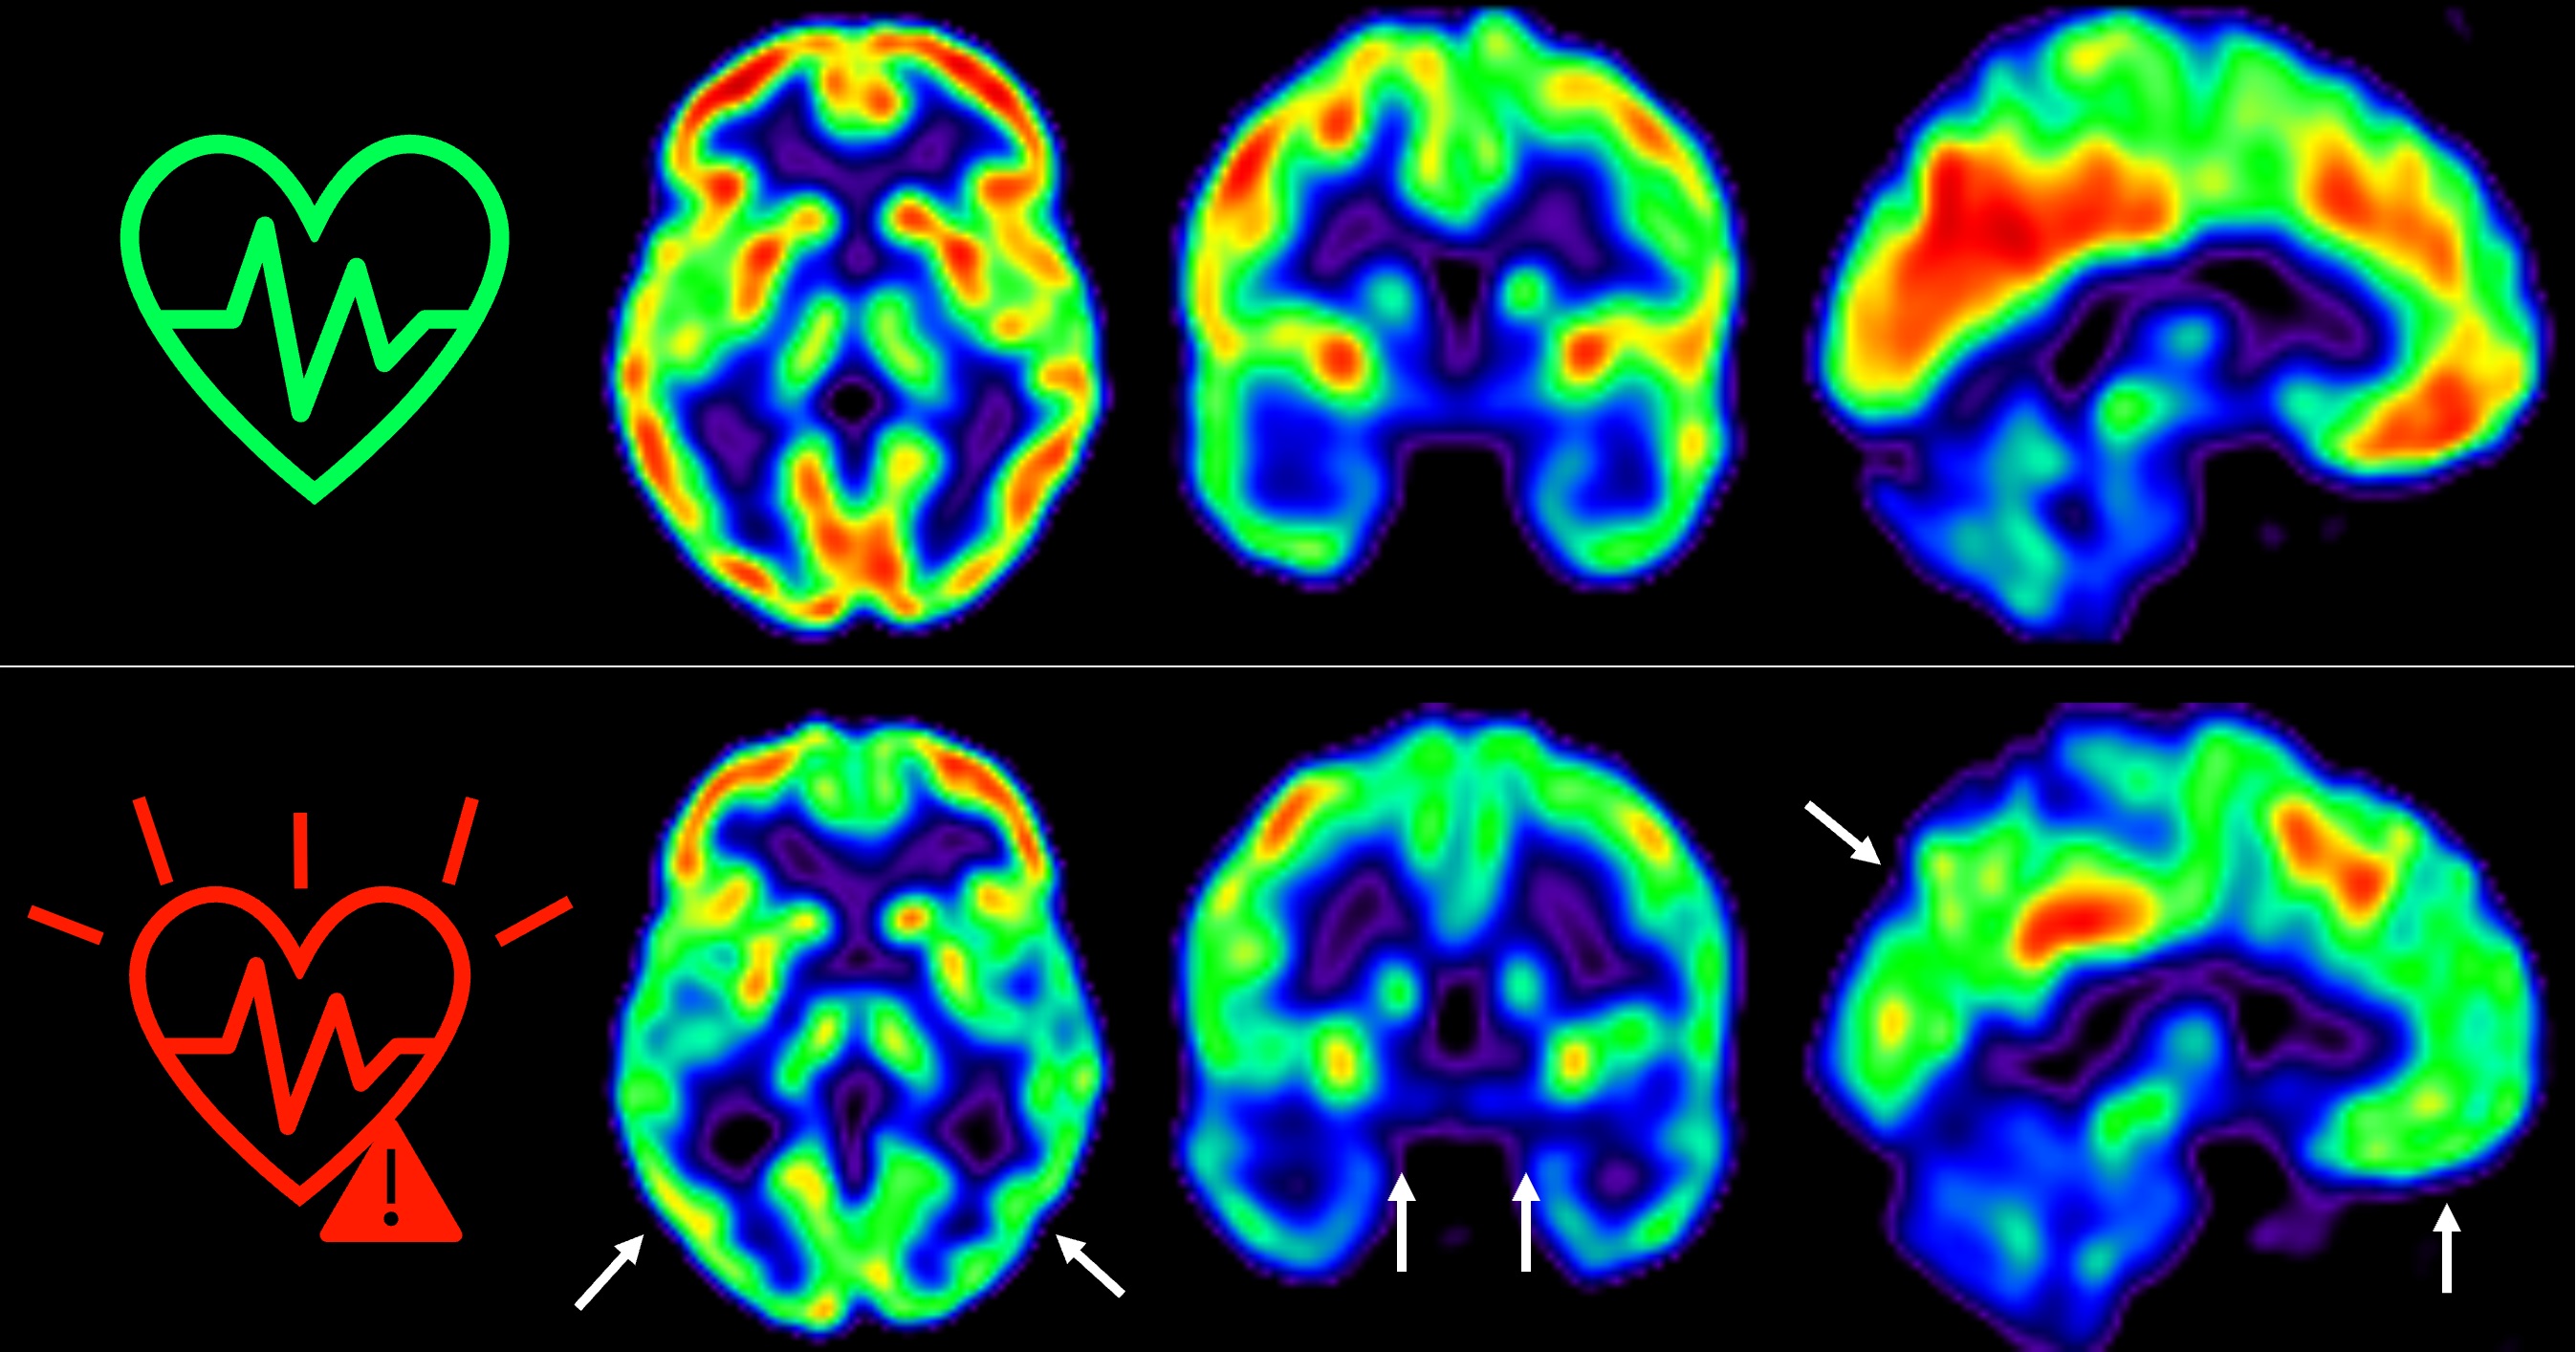

En 2021, los investigadores del CNIC descubrieron que la presencia de factores de riesgo cardiovascular y de aterosclerosis subclínica -antes de que aparezcan los síntomas- en las arterias carótidas, que son las que suministran sangre al cerebro, en individuos de 50 años aparentemente sanos que participan en el estudio PESA-CNIC-Santander, estaba asociada a un menor metabolismo de glucosa cerebral (Cortés-Canteli & Gispert et al. JACC. 2021). El metabolismo de la glucosa cerebral está considerado un indicador de salud cerebral.

El equipo, liderado por los Drs. Marta Cortés Canteli y Juan Domingo Gispert, ha seguido a estos individuos a lo largo de 5 años y han encontrado que aquellos que mantienen un riesgo cardiovascular elevado durante todo este tiempo sufren una disminución aún mayor del metabolismo cerebral medido a través de técnicas de imagen como tomografía por emisión de positrones (PET).

Hemos detectado un declive metabólico cerebral tres veces mayor que el de personas que se mantienen en bajo riesgo cardiovascular”, señala Catarina Tristão-Pereira, primera firmante del artículo y becaria INPhINIT de la Fundación ”la Caixa.

Además, el equipo descubrió que la progresión de la aterosclerosis subclínica en las carótidas durante estos 5 años se relacionaba con una disminución del metabolismo en regiones cerebrales vulnerables a la enfermedad de Alzheimer, de manera aditiva al efecto de los propios factores de riesgo cardiovascular. “Estos resultados corroboran que la detección por imagen de la aterosclerosis subclínica aporta información muy relevante”, añade el Dr. Fuster, investigador Principal del estudio PESA. “La relación entre el cerebro y el corazón es un tema fascinante y con este estudio hemos visto que empieza mucho antes de lo que se creía”, continúa.